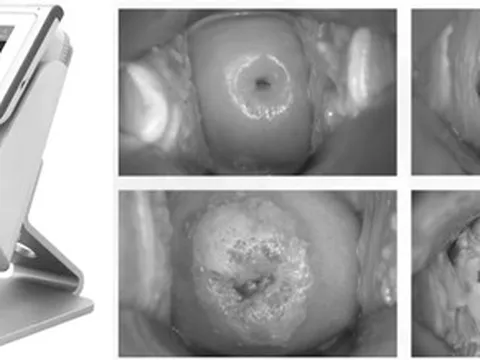

Cảnh báo sự nguy hiểm của bệnh đậu mùa khỉ

Tìm hiểu về các triệu chứng, dấu hiệu nhận biết và giải pháp phòng ngừa bệnh đậu mùa khỉ có thể giúp giảm mức độ nguy hiểm của bệnh.

Việt Nam có ca đậu mùa khỉ, chuyên gia nói “không được chủ quan”

Việt Nam vừa ghi nhận 2 ca mắc đậu mùa khỉ, PGS.TS Trần Đắc Phu cho rằng cần tiếp tục điều tra dịch tễ, giám sát ca bệnh.

2 ca mắc đậu mùa khỉ, Bộ Y tế đề nghị xác định nguồn lây

Cục Y tế dự phòng vừa có văn bản đề nghị các đơn vị liên quan nhanh chóng xác định nguồn lây, tăng cường công tác phòng, chống bệnh đậu mùa khỉ sau khi Việt Nam ghi nhận thêm 2 ca mắc

Ghi nhận 2 ca đậu mùa khỉ, Bộ Y tế đề nghị xác định nguồn lây

Bộ Y tế đề nghị các đơn vị liên quan khẩn trương điều tra kỹ tất cả các trường hợp tiếp xúc với trường hợp dương tính với đậu mùa khỉ để xác định nguồn lây nhiễm.